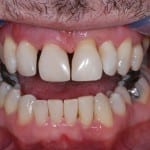

If part of a tooth has been lost through decay or damaged due to an accident, your dentist can repair it with a filling.

A filling will plug the hole and stop future pain or discomfort. There are a variety of materials, the most common of which are amalgam (silver) and composite (white) although we are increasingly using highly aethetic and strong ceramic fillings made with our CEREC system.  We are the only practice in Harrogate and Knaresborough who are able to offer this technology

Many people opt for white fillings which match the colour of the natural tooth. White fillings are a great way to repair teeth without spoiling their appearance, and can also be used to improve the appearance of badly shaped and  ‘gappy’ teeth.